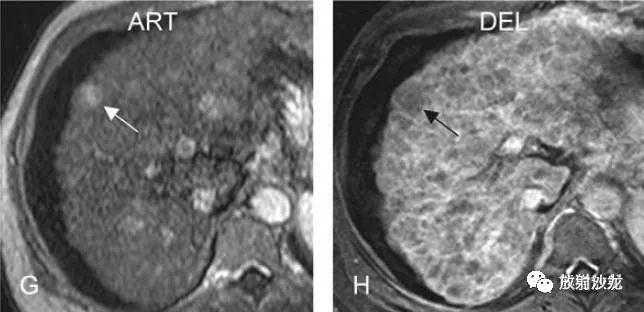

DN-HCC转变,MRI随访(18个月后):

A:T2压脂可见类圆形高信号灶;

F:同反相位示病灶内无明显脂肪浸润;

G:动脉期,结节明显均匀强化;

H:延迟期,结节内造影剂廓清,周围可见肿瘤假包膜,符合HCC表现。